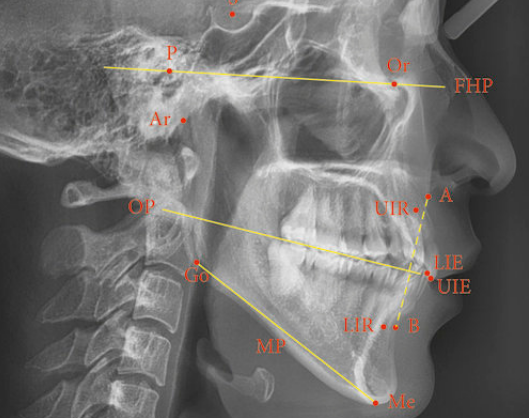

Diagnosis:

- Photography.

- Lateral Cephalometry.

- Space Analysis.

- Indices.